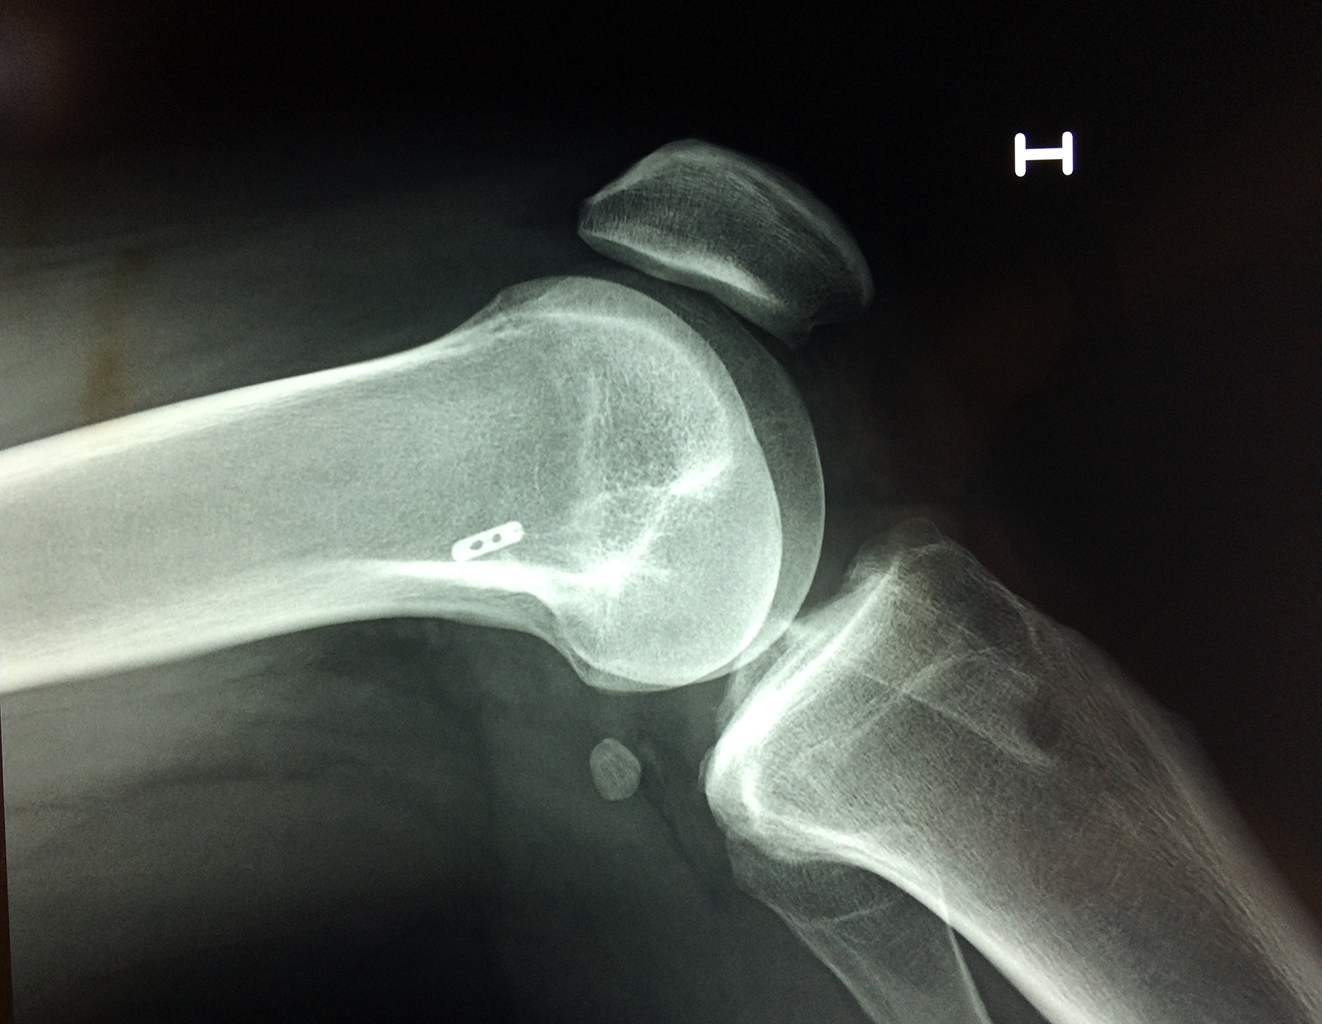

La artroscopia de rodilla es un cirugía en el cual la estructura interna de la articulación es examinada ya sea para realizar un diagnostico o para realizar un tratamiento, este procedimiento se realiza utilizando un instrumento parecido a un pequeño tubo llamado artroscopio.

La artroscopia se popularizo en 1960 y hoy en día es muy común en todo el mundo. Típicamente, es realizada por cirujanos ortopédicos de manera ambulatoria. Cuando se realiza de manera ambulatoria los pacientes pueden regresar a casa después de la operación, no se requiere quedarse en hospital.